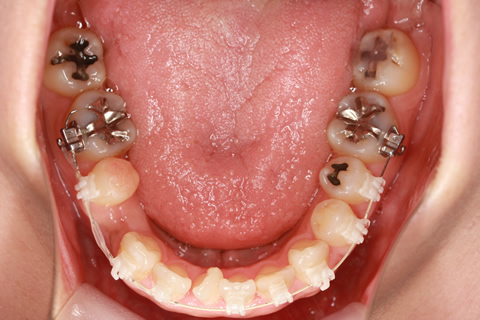

矯正の症例 受け口(反対咬合)

受け口(反対咬合)の症例

症例一覧